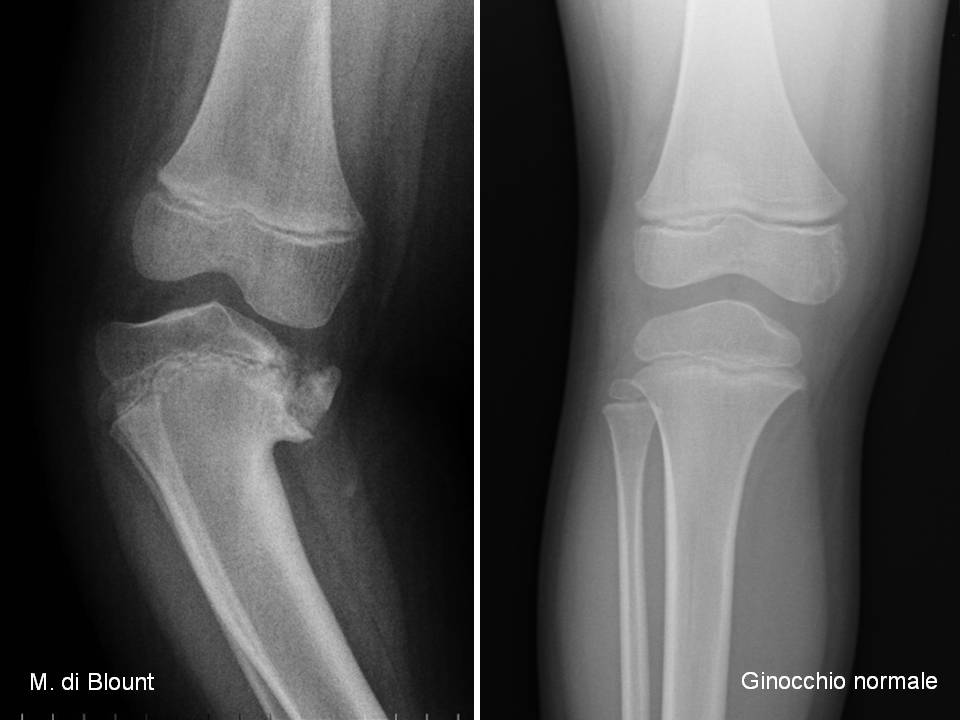

Fig 12. RX morbo di Blount e ginocchio normale ← Precedente Successivo → Fig .12: RX morbo di Blount e ginocchio normale